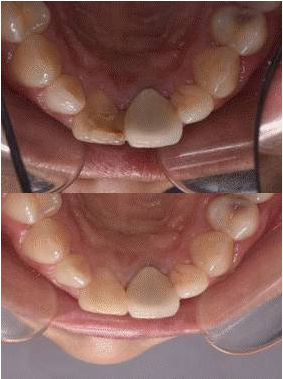

11去除暫封材料,清理髓腔,選擇性釉質(zhì)酸蝕,涂自酸蝕粘結(jié)劑,牙本質(zhì)色樹(shù)脂充填牙本質(zhì)層,牙釉質(zhì)色樹(shù)脂充填釉質(zhì)層,調(diào)牙合修形,拋光。圖10[1]/11/12(停止漂白后,需等待2周以上[2],以使顏色穩(wěn)定、氧氣消散及恢復(fù)粘結(jié)力,若患者時(shí)間緊迫,為了中和過(guò)氧化物的氧化性,也可用過(guò)氧化氫酶沖洗髓腔,或應(yīng)用氫氧化鈣覆蓋髓腔2天)

圖10 復(fù)合樹(shù)脂充填

圖11 治療后唇側(cè)觀

圖12 治療后舌側(cè)觀

圖13 治療前后唇面對(duì)比

圖14 治療前后舌側(cè)對(duì)比